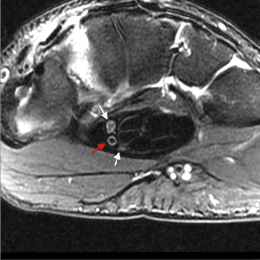

A à D - IRM coupe axiale T2 du poignet : Aspect bi-partite en rapport avec une division précoce du nerf médian au sein du canal carpien. Présence d'une artère (avec hyposignal central) entre les 2 portions nerveuses (flèches rouges).

Nerf médian : division précoce et avec persistance d'une artère du nerf médian (asymptomatique).